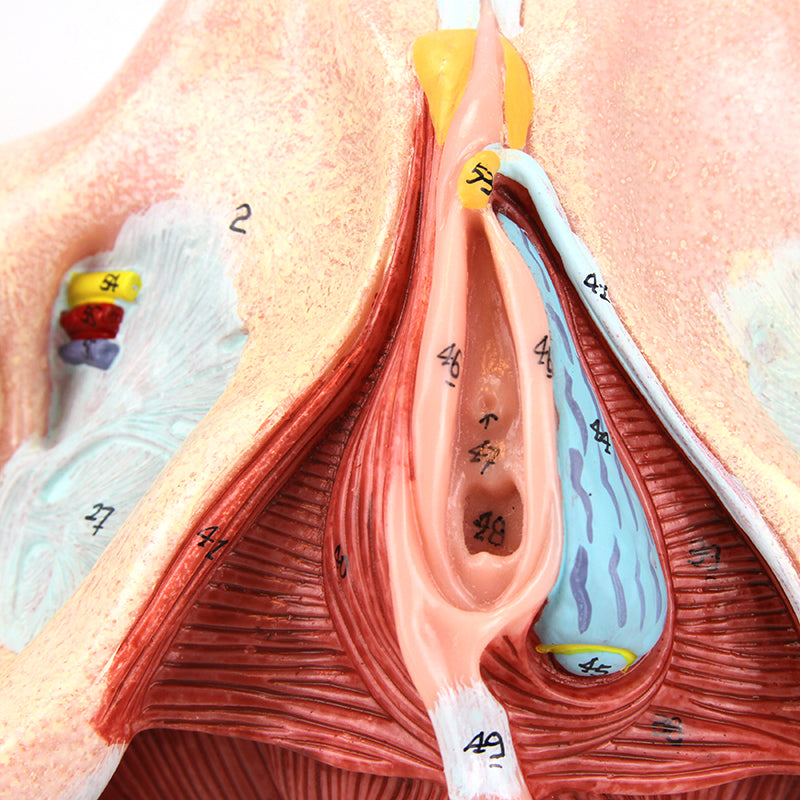

女性骨盤モデル(靭帯、血管、神経、骨盤底筋付き)

この実物大の女性骨盤は、仙腸靭帯、骨盤底筋、神経網および仙骨血管とともに、骨盤の外性器および内性器の構造を手描きで示しています。筋肉や靭帯の筋理を細かく描写しており、このモデルに高品質で詳細な印象を与えています。このモデルは女性の骨格系を理解するための優れた学習教材であり、すべての学生に適しています。さらに、神経痛、筋肉の緊張、靭帯の損傷を患者に説明する際にも役立ちます。拡張現実を用いたインタラクティブな三次元解剖モデルと併用することで、学習を促進し支援する優れたツールとなります。このプラットフォームは、学生が個々の器官の構造を比較・対照しながら解剖モデルの比較分析に取り組むことを可能にします。また、この取り組みは継続教育の場を提供し、すべての学生が解剖学、生理学および病理生理学の知識を深める機会を提供します。

女性骨盤モデル(靭帯、血管、神経、骨盤底筋付き)

この実物大の女性骨盤は、仙腸靭帯、骨盤底筋、神経網および仙骨血管とともに、骨盤の外性器および内性器の構造を手描きで示しています。筋肉や靭帯の筋理を細かく描写しており、このモデルに高品質で詳細な印象を与えています。このモデルは女性の骨格系を理解するための優れた学習教材であり、すべての学生に適しています。さらに、神経痛、筋肉の緊張、靭帯の損傷を患者に説明する際にも役立ちます。拡張現実を用いたインタラクティブな三次元解剖モデルと併用することで、学習を促進し支援する優れたツールとなります。このプラットフォームは、学生が個々の器官の構造を比較・対照しながら解剖モデルの比較分析に取り組むことを可能にします。また、この取り組みは継続教育の場を提供し、すべての学生が解剖学、生理学および病理生理学の知識を深める機会を提供します。